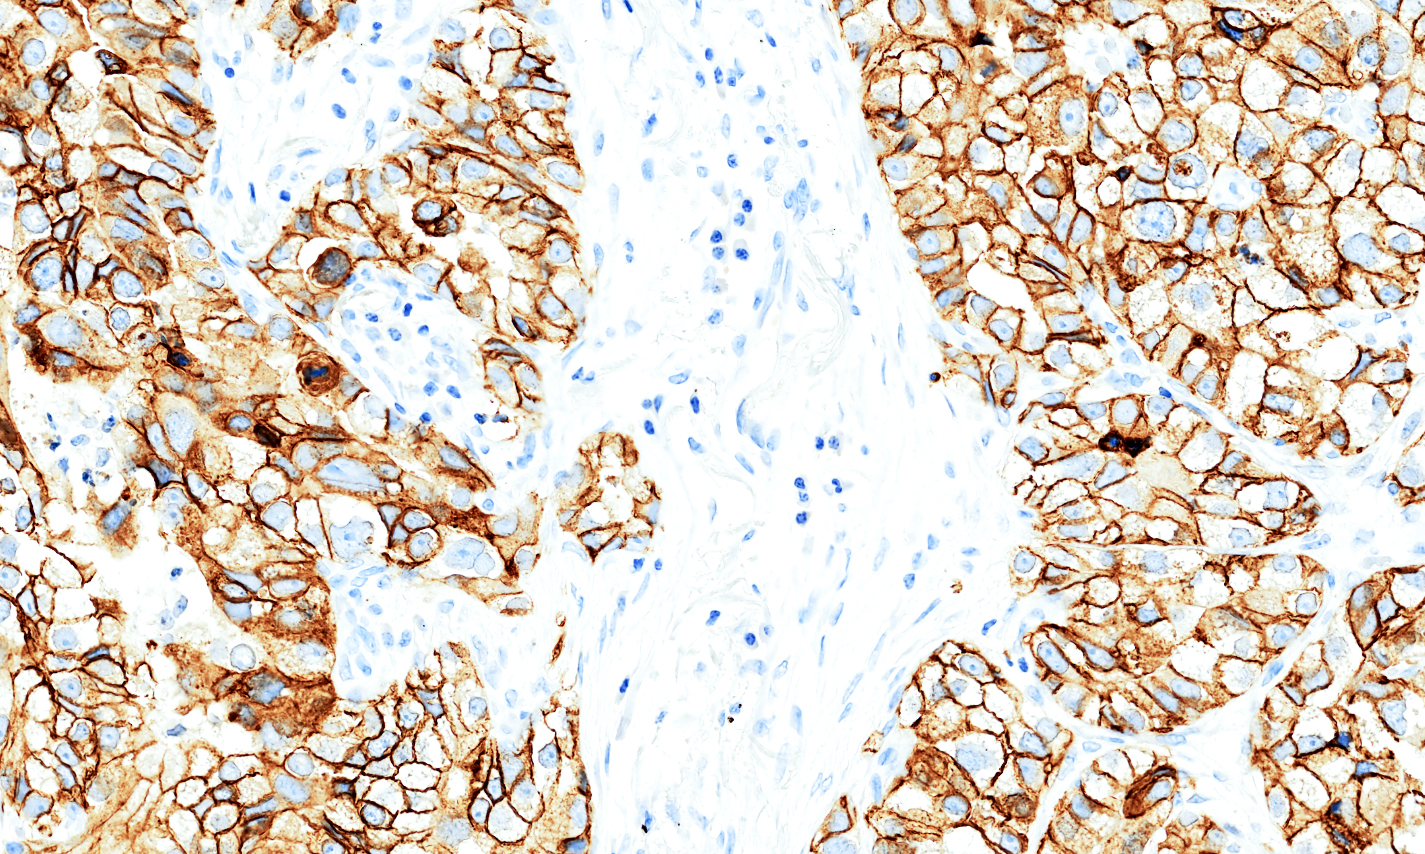

Predominantly membranous positivity in the neoplastic cells of basal cell carcinoma.